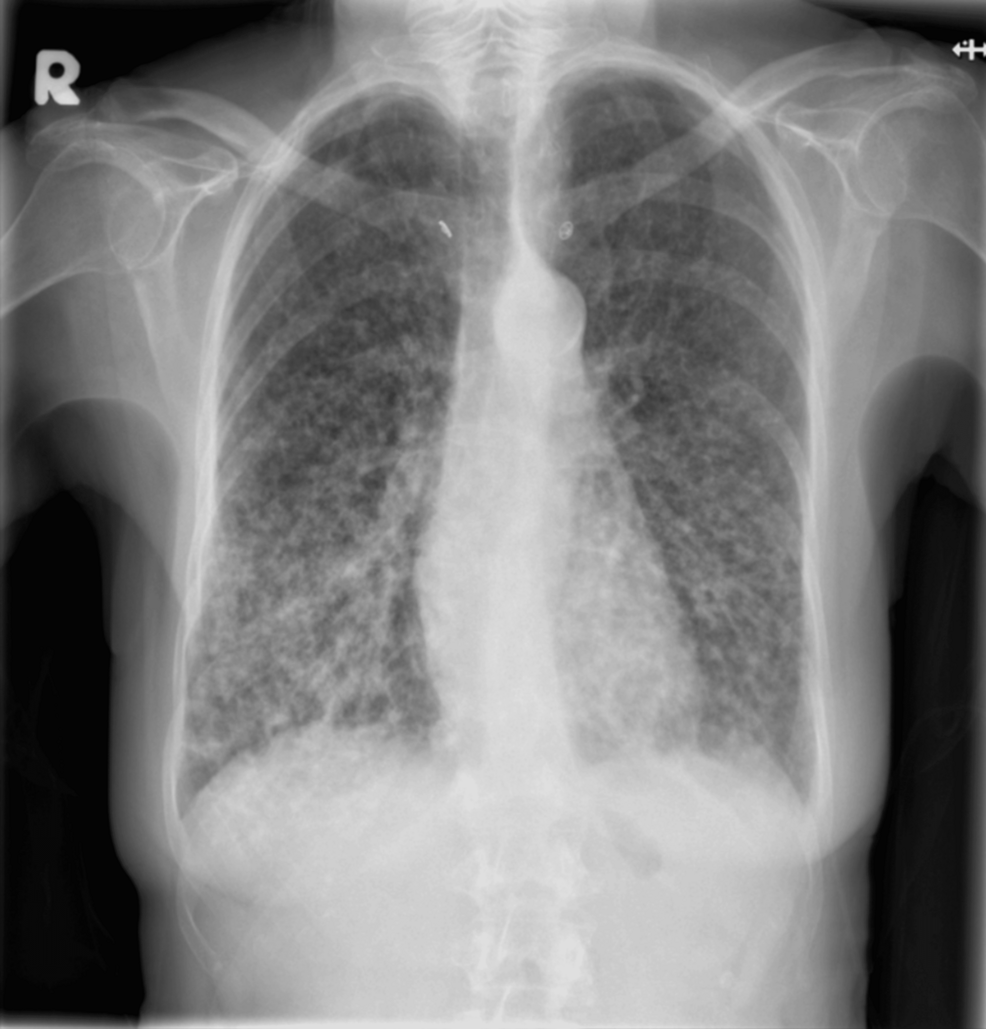

- 文献精读丨影像学随访是否已过时?ctDNA检测阳性如何预示低风险HR阳性乳腺癌患者晚期复发? 一项发表于Int J Mol Sci 期刊的病例研究介绍了1例在随访期进行ctDNA监测的低危激素受体阳性(HR+)乳腺癌患者的诊疗经过。本文系统整理了该病例的核心临床数据、治疗决策过程及ctDNA动态监测结果,以飨读者。……